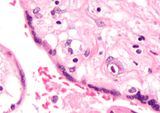

Micrograph of a placental infection (CMV placentitis).